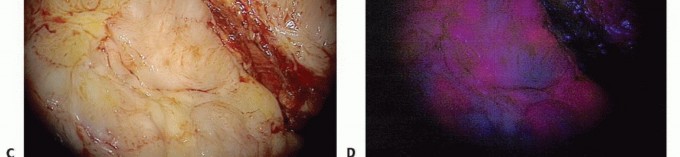

الاستئصال الموجه (Image-Guided Ablation) بتقنية العلاج الضوئي الديناميكي (PDA): نهج ثوري

يمثل الاستئصال الموجه باستخدام العلاج الضوئي الديناميكي (Photodynamic Ablation - PDA) قفزة نوعية في علاج أورام الجهاز العضلي الهيكلي. هذه التقنية المبتكرة توفر حلاً دقيقًا وموجهًا، يتجاوز العديد من التحديات والمضاعفات المرتبطة بالعلاجات التقليدية.

في هذا السياق، يبرز الاستئصال الموجه (Image-Guided Ablation) باستخدام تقنية العلاج الضوئي الديناميكي (Photodynamic Ablation - PDA) كنهج علاجي ثوري يوفر حلًا أكثر أمانًا وفعالية. هذه التقنية المبتكرة لا تستهدف الأنسجة السرطانية بدقة متناهية فحسب، بل تقلل أيضًا من الضرر الذي يلحق بالأنسجة السليمة المحيطة، مما يفتح آفاقًا جديدة للمرضى الذين يعانون من أورام الجهاز العضلي الهيكلي، ويقدم لهم فرصة لنتائج علاجية أفضل وجودة حياة محسنة بشكل ملحوظ.